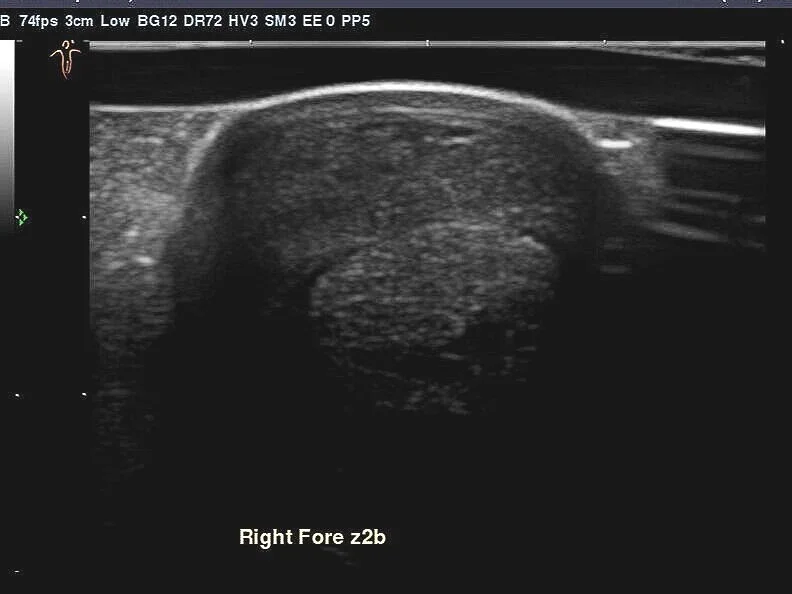

The images below show an injury to a five year old national hunt horse that had adipose derived stem cells implanted four weeks ago. These cells were harvested from subcutaneous fat located to the side of the tail base. This tissue yields far higher numbers of mesenchymal cells than bone marrow and they can be multiplied in the lab much quicker. As you can see the injury has filled in extremely well in a short time. Luckily this horse has a very patient owner who is prepared to give the mare a slow, controlled rehab program which should return her to the track.

Ultrasound scan showing damage to the superficial flexor tendon.

Four weeks post implantation of stem cells showing dramatic improvement in fibre pattern.